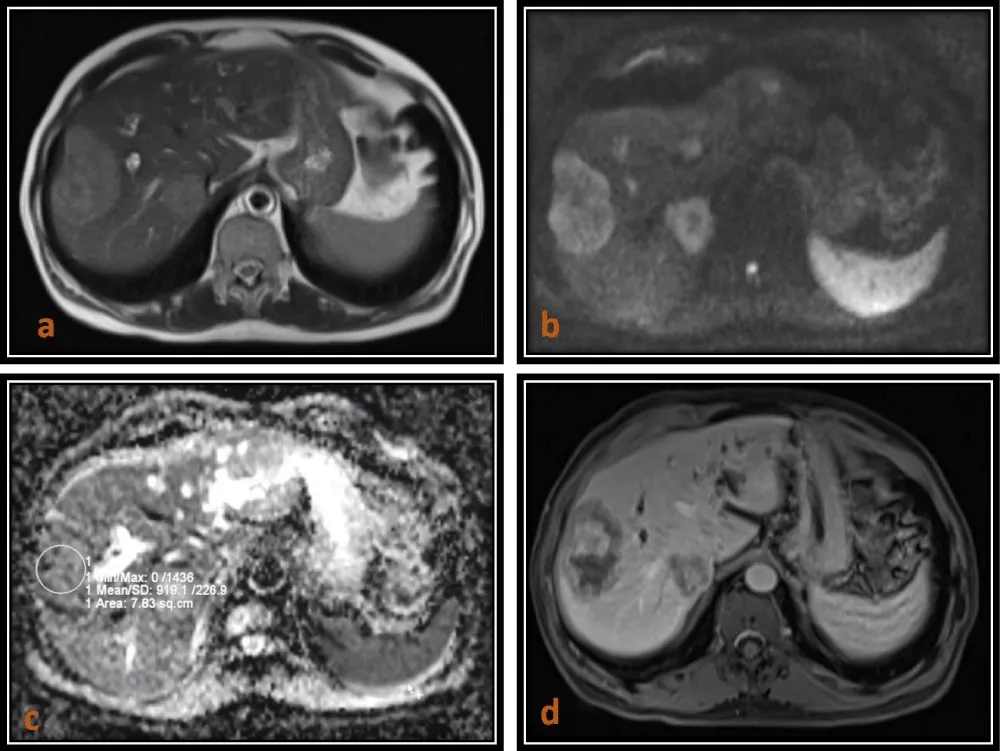

In our study, hepatic cysts demonstrated the highest ADC values, followed by hemangiomas, whereas malignant lesions such as HCC and metastases showed significantly lower ADC values. The mean ADC values of malignant lesions were significantly lower (0.90 ± 0.15 × 10-3 mm2/s) (Figures 1,2,4) than those of benign lesions (2.19 ± 0.29 × 10-3 mm2/s) (Figure 3), and this difference was statistically significant, in agreement with previous studies [10]. However, no significant difference was observed between primary (0.89 ± 0.15 × 10-3 mm2/s) and metastatic malignant lesions (0.90 ± 0.14 × 10-3 mm2/s), which may be attributed to the relatively small sample size.

Download Image

Figure 2: 65-year-old male patient with Intrahepatic Cholangiocarcinoma. (a) Axial T2(TruFISP)-weighted image shows a slightly hyperintense lesion in the right lobe of the liver, which is hyperintense on DWI (b = 800) as seen in image (b) and isointense to hypointense on the ADC map as seen in image (c)with a low ADC value (0.903 x 10-3 mm2/s).